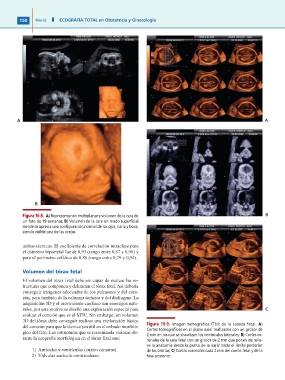

Figura 16-8. A) Representación multiplanar y volumen de la cara de

un feto de 19 semanas; B) Volumen de la cara en modo superficial

donde se aprecia una configuración normal de los ojos, nariz y boca,

siendo visible una de las orejas.

El volumen del tórax fetal debe ser capaz de evaluar las es- Figura 16-9. Imagen tomográfica (TUI) de la cabeza fetal. A)

conseguir imágenes adecuadas de los pulmones y del cora- Cortes tomográficos en el plano axial realizados con un grosor de

zón, pero también de la columna torácica y del diafragma. La 2 mm en los que se visualizan los ventrículos laterales; B) Cortes co-

adquisición 3D y el movimiento cardiaco son enemigos natu- ronales de la cara fetal con un grosor de 2 mm que ponen de relie-

rales, por este motivo se diseño una exploración especial para ve la anatomía desde la punta de la nariz hasta el límite posterior

evaluar el corazón que es el STIC. Sin embargo, un volumen de las órbitas; C) Cortes coronales cada 2 mm del cuello fetal y de la

3D del tórax debe conseguir realizar una exploración básica fosa posterior.